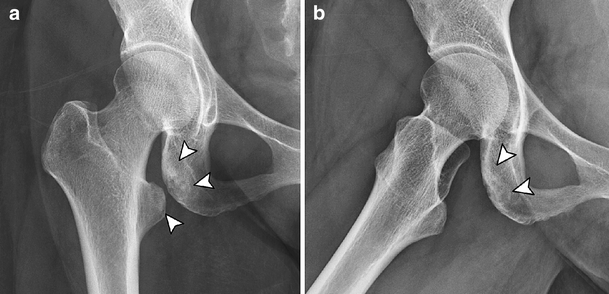

Lesser Trochanter Of Right Femur : A&P Lab Exam 3: Bones at Olympic College - StudyBlue / It projects from the lower and back part of the base of the femur neck.. The lesser trochanter is also called the minor trochanter, the inner trochanter, and the medial process of the femur. It is the insertion point for the iliacus and psoas major muscles. The greater trochanter gives attachment to a number of muscles (including the gluteus medius and minimus, piriformis, obturator internus and externus, and gemelli muscles). The lesser trochanter of the femur is a conical eminence, which varies in size in different species. Over 65000 hip fractures each year are recorded occur in the uk alone and they are neck of femur (nof) fractures can occur anywhere from the subcapital region of the femoral head to 5cm distal to the lesser trochanter (fig.

Intertrochanteric fracture of the femur | Image ... from images.radiopaedia.org The lesser trochanter (small trochanter) of the femur is a conical eminence, which varies in size in different subjects. Lesser trochanter (plural lesser trochanters) a small eminence on the proximal femur, below the greater trochanter. Lesser trochanter of femur the body bones greater trochanter of femur fifth lumbar vertebra. The shaft of the femur is gradually convex anteriorly with maximum convexity in the middle third where the shaft is narrowest. Clinically, the displaced lesser trochanter is usually not reduced when intramedullary fixation is used in the treatment of unstable trochanteric fractures. Greater trochanter of femur a: Over 65000 hip fractures each year are recorded occur in the uk alone and they are neck of femur (nof) fractures can occur anywhere from the subcapital region of the femoral head to 5cm distal to the lesser trochanter (fig. The greater trochanter gives attachment to a number of muscles (including the gluteus medius and minimus, piriformis, obturator internus and externus, and gemelli muscles).

Lesser trochanter bsis are less common compared with femoral neck bsis. Ebraheim's educational animated video describes anatomy and how to draw the femur. It receives the insertion of the psoas major and there are 2 trochanters (greater and lesser) both are prominences found on the upper aspect of the femur (thigh bone) between the shaft and neck. Read in detail about femur anatomy. The lesser trochanter is more clearly visible on the right indicating external rotation of the femur, a finding that is suspicious for a femoral neck fracture.

The greater trochanter gives attachment to a number of muscles (including the gluteus medius and minimus, piriformis, obturator internus and externus, and gemelli muscles). It projects from the posteromedial side of the femur, just after it passes the lesser trochanter on the posterior surface, it is known as the pectineal line. Subscribe to learn interesting facts about the human body every day. The lesser trochanter (small trochanter) of the femur is a conical eminence, which varies in size in different subjects. A fractured neck of femur (nof) is a common orthopaedic presentation. Over 65000 hip fractures each year are recorded occur in the uk alone and they are neck of femur (nof) fractures can occur anywhere from the subcapital region of the femoral head to 5cm distal to the lesser trochanter (fig. Two of these are above—a medial continuous with the lower border. The lesser trochanter (trochanter minor; Non displaced minimally impacted subcapital right neck of femur fracture. The lesser trochanter of the femur is a conical eminence, which varies in size in different species. Femur is bone that extends from hip to knee joint and is also called thigh bone. As a long bone, the femur consists of a narrow shaft that is capped at either end by multiple rounded projections. Greater trochanter of femur a: